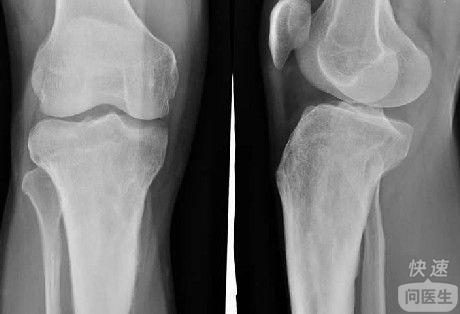

核心提示:胫骨结节骨软骨炎 本病又称胫骨结节骨骺炎或骨软骨炎、无菌性坏死、牵引性骨骺炎,是一种少年的疾患,患儿的胫骨结节变大伴疼痛。那么胫骨结节骨软骨病有哪些症状呢?得了胫骨结节骨软骨病吃什么好,同时又不能吃什...